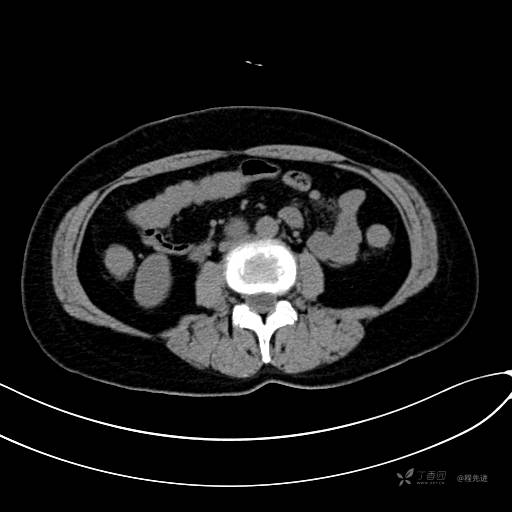

CT增强动脉期